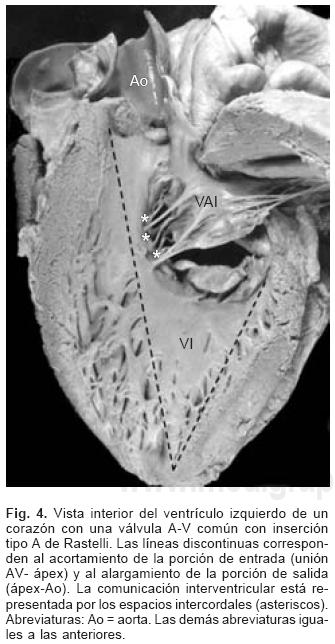

Sesenta y cinco corazones (92.86%) presentaron una válvula A–V dentro de un anillo fibroso A–V común (Fig. 3A) y los cinco restantes (7.14%) presentaron dos válvulas A–V separadas derecha e izquierda dentro del anillo fibroso común (Fig. 3B). La válvula A–V común estuvo constituida por cinco valvas, dos anterosuperiores derecha e izquierda, dos laterales derecha e izquierda y una posterior común; en estos corazones la CIV fue permeable (Fig. 2A), la distancia entre la unión A–V y el ápex estuvo disminuida y la distancia entre el ápex y la válvula aórtica aumentada (Fig. 4); la división entre ambos valores dio como resultado un cociente menor de uno.

De los sesenta y cinco corazones con válvula común en veinticinco se determinaron los tipos de la clasificación de Rastelli que fueron los siguientes: en once (44%) las valvas anterosuperiores derecha e izquierda se insertaron a través de sus cuerdas tendinosas sobre la cresta del tabique ventricular y la CIV se ubicó en los espacios intercordales (tipo A de Rastelli) (Figs. 1A y 5A). En un espécimen las valvas anterosu–periores izquierda (valva puente) y derecha se insertaron sobre la cara derecha del tabique ventricular por debajo de su cresta (Fig. 5B) y en otro dicha inserción se hizo en la parte superior del cuerpo de la trabécula septomarginal (Fig. 5C). En ocho corazones (32%) la inserción de esas valvas se estableció en un músculo papilar situado en la unión del tabique ventricular con la pared libre del ventrículo derecho y la valva anterosuperior izquierda pasó como puente por encima de la CIV (tipo B de Rastelli) (Figs. 1B y 5D) y en seis corazones (24%) la inserción de las valvas anterosuperior izquierda (valva puente) y derecha se insertaron en un músculo papilar de la pared libre del ventrículo derecho y esta valva se ubicó por encima de la CIV (tipo C de Rastelli) (Figs. 1C y 5E). En los cuarenta corazones restantes no fue posible determinar los tipos de Rastelli debido a que treinta y tres de ellos presentaron doble entrada ventricular (Fig. 6A) dos tuvieron modificaciones anatómicas generadas por la cirugía y cinco por presentar mutilaciones realizadas durante la necropsia. Los cinco especímenes con dos válvulas separadas tuvieron estructura trifoliada dentro de la unión A–V común (Figs. 3B y 6B); la válvula A–V izquierda mostró una valva lateral y dos septales anterior y posterior unidas a la cresta del tabique ventricular, lo que obliteró la CIV (Fig. 6C). La válvula A–V derecha mostró una valva septal displásica, una anterior y una posterior (Figs. 3B y 6B).

La anatomía básica de los 2 tipos de DSA–V fue la misma. Todos presentaron anillo fibroso A–V común, reducción de la distancia A–V–ápex e incremento de la distancia ápex –válvula aórtica, el tabique ventricular estuvo excavado (Figs. 4 y 6C), el anillo fibroso mostró dilatación anteroposterior, desencuñamiento aórtico, alteración en el esqueleto fibroso del corazón consistente en un anillo fibroso A–V común, ausencia del septum membranoso y persistencia de la continuidad entre la válvula aórtica y la válvula A–V común o válvula A–V izquierda (Fig. 6D), desviación anterior del tracto de salida del ventrículo izquierdo (Figs. 4 y 6C) y en dos especímenes obstrucción de éste por inserción en su interior de la valva anterosuperior izquierda (Fig. 7A). En un espécimen con una válvula A–V común se desarrolló una banda anómala de miocardio entre la pared libre y el tabique ventricular, lo que separó el componente derecho de la válvula A–V común en dos orificios valvulares (Fig. 7B). Las alteraciones asociadas se consignan en la Tabla III.

Debido al DSA–V y a la deficiencia del tabique ventricular, éste muestra un aspecto excavado con disminución de la porción de entrada y alargamiento del tracto de salida; cuando se divide el valor de la primera entre el de la segunda el índice obtenido es inferior a la unidad y entre más corta sea la porción de entrada más larga es la salida del ventrículo izquierdo.2,9 En un corazón normal el coeficiente es muy cercano a la unidad ya que ambas distancias casi son equidistantes. Este hecho tiene una gran importancia ya que el alargamiento del tracto de salida y su desplazamiento anterior condiciona un estrechamiento en el mismo y en ciertas ocasiones la valva anterior izquierda puede enviar sus cuerdas tendinosas hacia el interior de dicho tracto, lo que produce obstrucción subaórtica como ocurrió en dos corazones de esta serie. Se ha referido en la literatura que aquellos casos con tracto de salida muy alargado presentan riesgo potencial de obstrucción postquirúrgica.9,24 El alargamiento del tracto de salida y su desplazamiento anterior constituyen la base anatómica del signo angiográfico de "cuello de ganso", patognomónico de esta cardiopatía.25